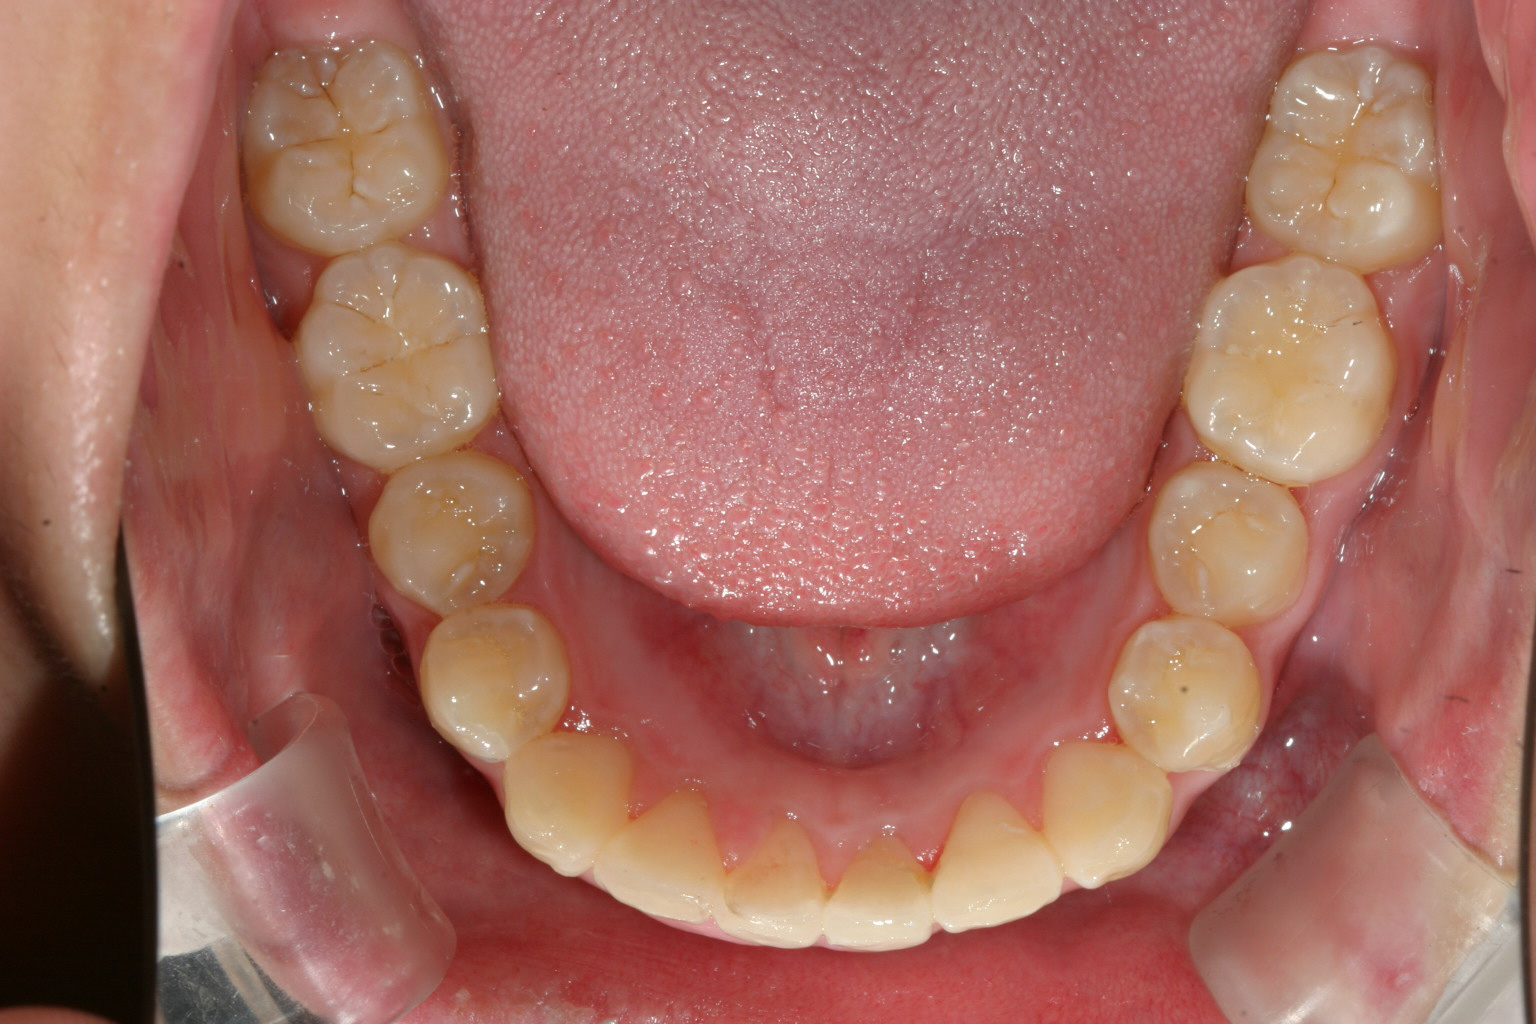

咬合面観はさほど悪く無いように見えます。

前歯部に少し乱れが有ります。